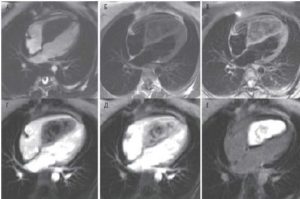

Рисунок 2. МРТ. Аневризма нисходящего отдела аорты.

Рисунок 3. МРТ. Четырехкамерное сечение сердца. Апикальная гипертрофия миокарда левого желудочка.

Рисунок 4. МРТ. Четырехкамерное сечение сердца. Миокардит, субэпикардиальное и интрамиокардиальное накопление контрастного препарата.

Рисунок 5. МРТ. Двухкамерное сечение левого желудочка. Постинфарктный кардиосклероз.